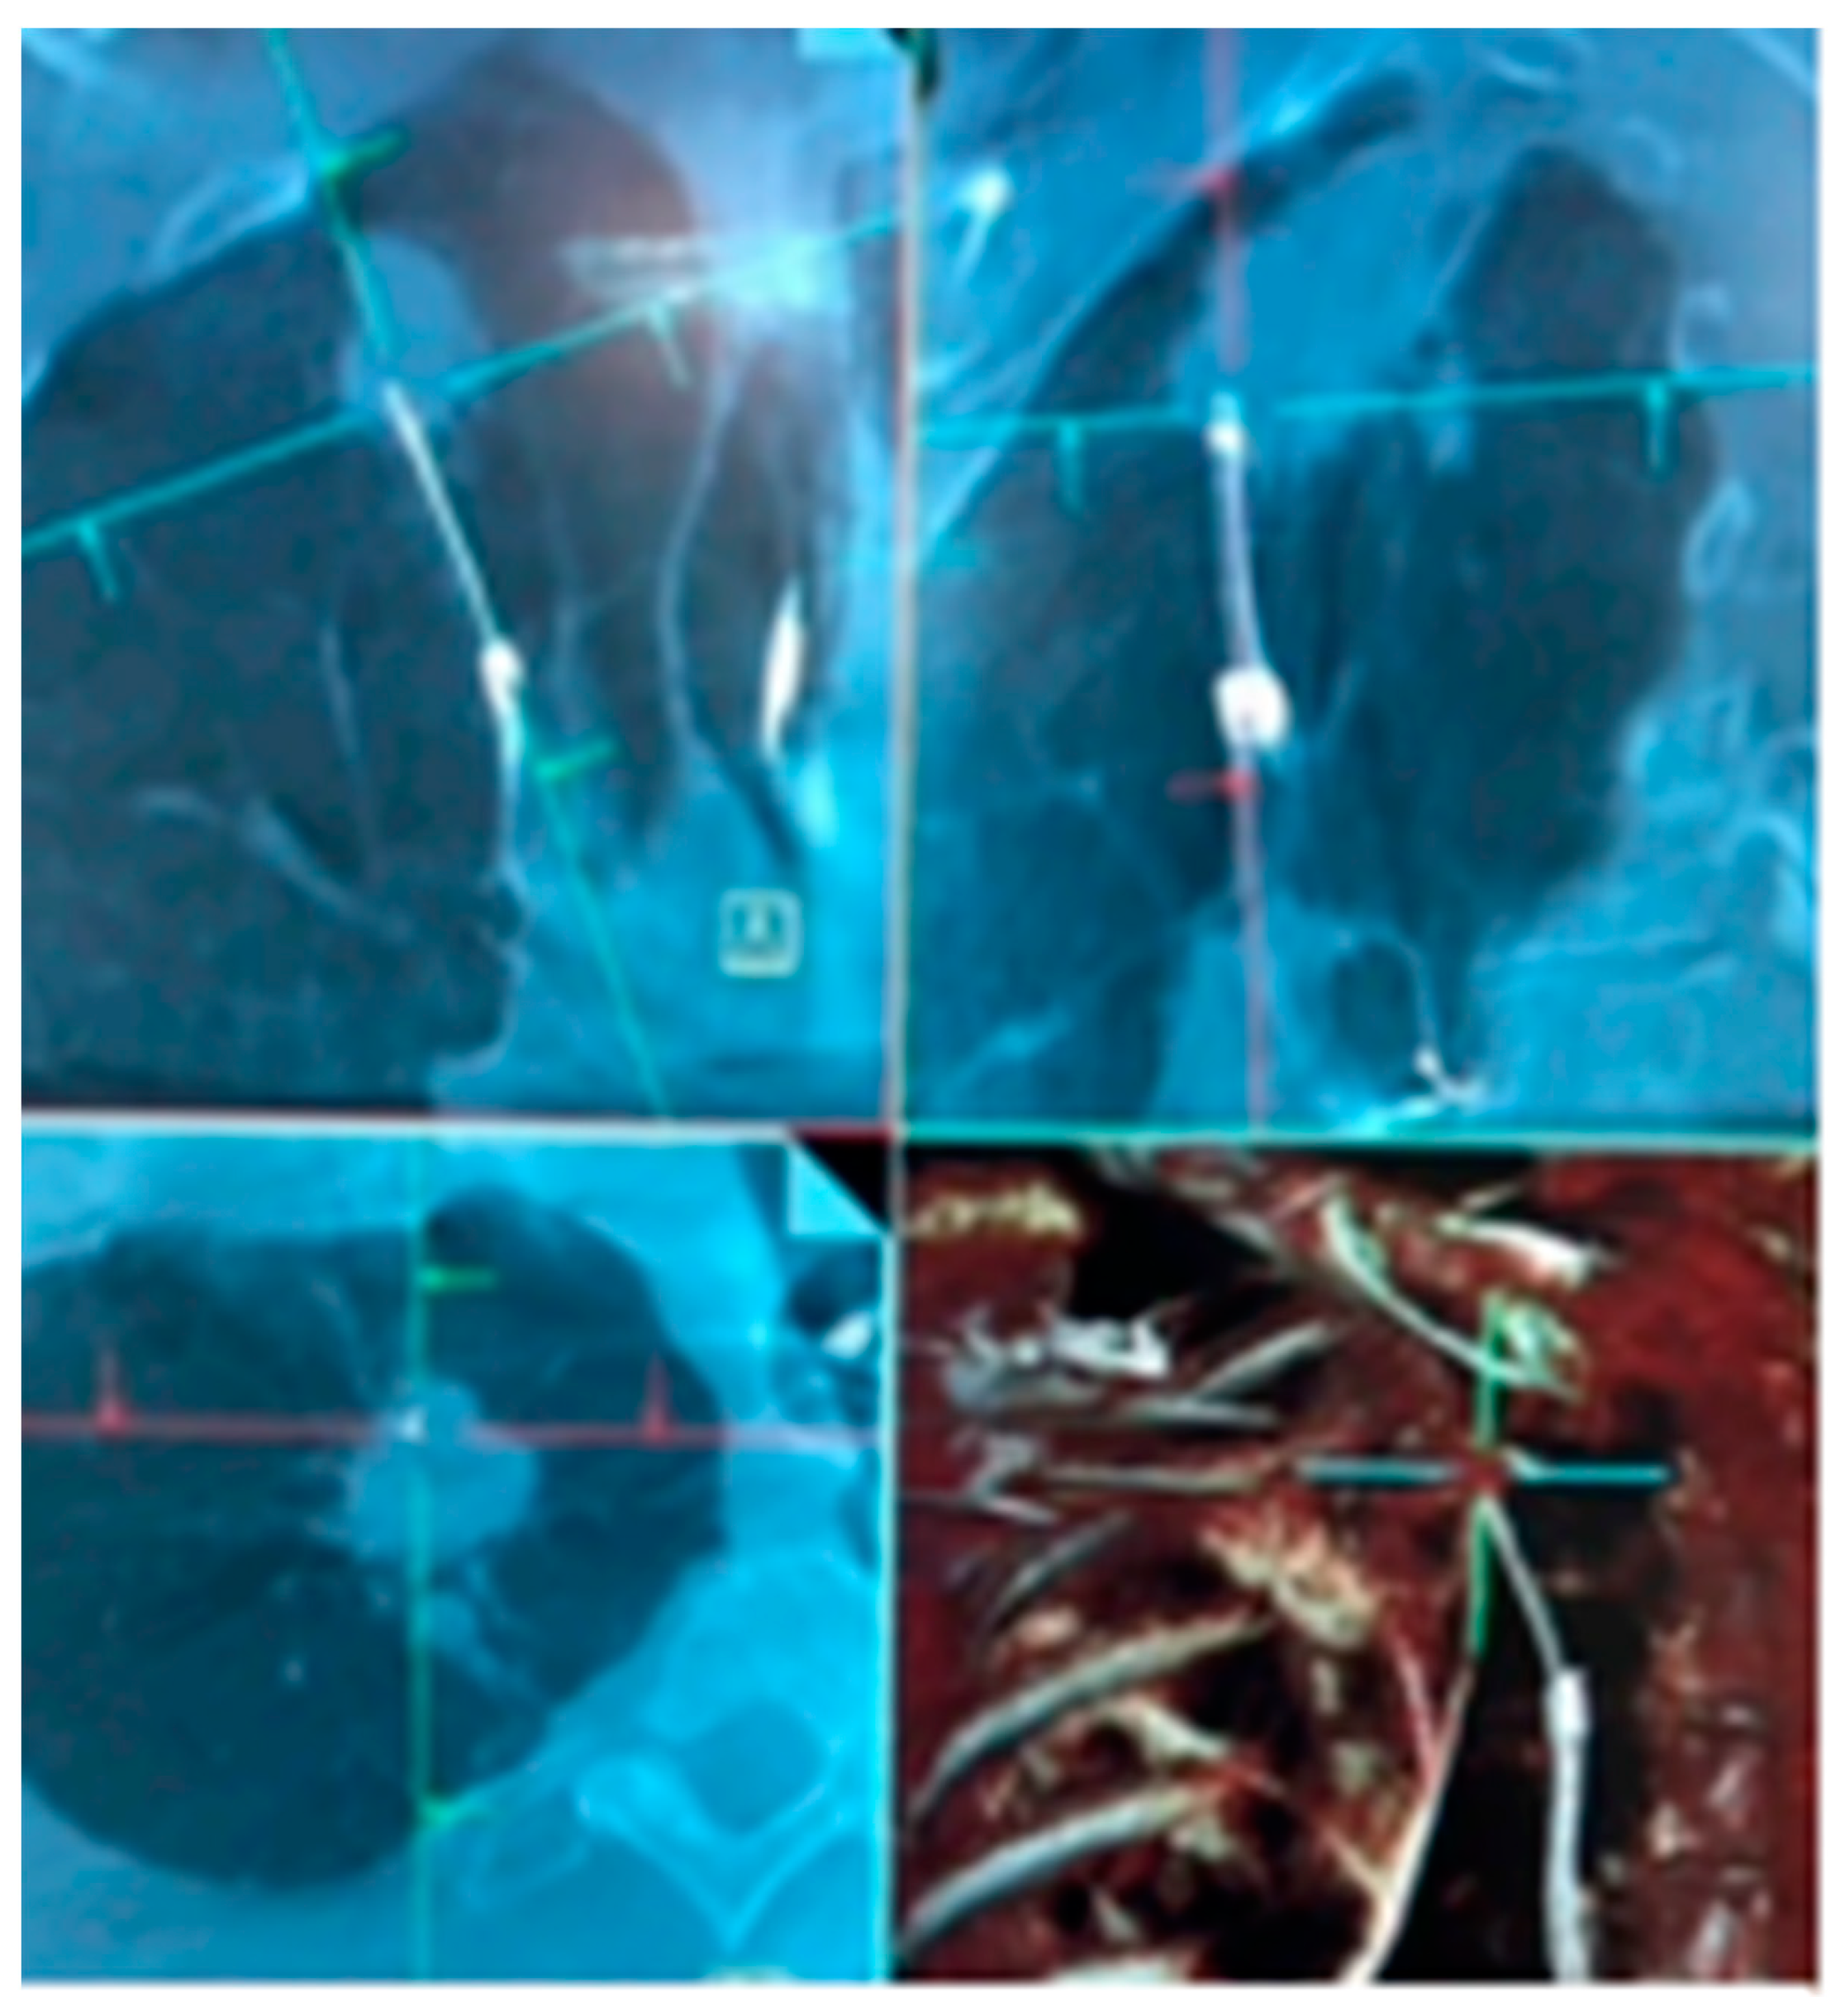

3.2.1. Ion™ Robotic Platform Combined with CBCT

- Hedstrom, G.; Wagh, A.A. Combining Real-time 3-D imaging and augmented fluoroscopy with robotic bronchoscopy for the diagnosis of peripheral lung lesions. Chest 2022, 162, A2082. [Google Scholar] [CrossRef]

| Hedstrom et al. [19] | Monarch™ robotic platform with lung vision | Robotic platform for navigation with CABT from Lung vision for intra-procedural real-time guidance | 45 patients | DYi: 84% DA: 91% | Pneumothorax: 8% (4/45) |